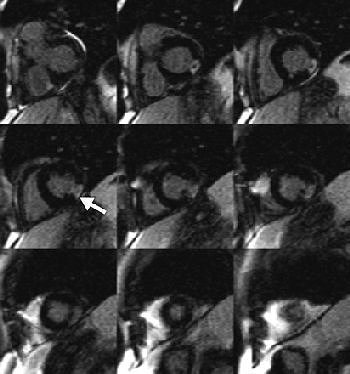

![]() |

| Sixty-seven-year-old man with transmural myocardial infarction after occlusion of circumflex artery. Nine MR images, acquired with inversion-recovery true fast imaging with steady-state precession (trueFISP) during a single breath-hold, reveal transmural infarction (arrow) as hyperenhanced region in inferolateral segments. Huber A, Schoenberg S, Spannagl B, Rieber J, Erhard I, Klauss V, Maximilian F, Reiser M, "Single-Shot Inversion Recovery TrueFISP for Assessment of Myocardial Infarction" (AJR 2006; 186:627-633). |